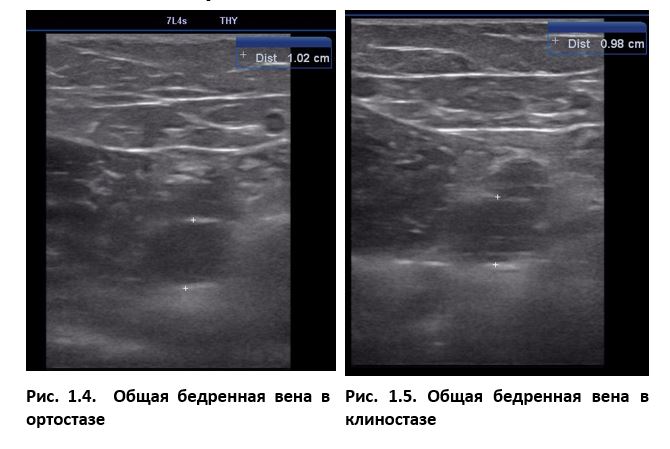

Ультразвуковое исследование вен нижних конечностей мы всегда проводим в положении больного стоя (ортостаз). Только так возникает достаточное ортостатическое давление на венозные клапаны, которое вызовет рефлюкс в случае их несостоятельности. Одновременно, варикозно расширенные вены лучше визуализируются в этом положении, а их подкожное расположение позволяет в комплексе с ультразвуковой картиной правильно оценить распространение патологии. Так же, в положении стоя мы проводим ультразвуковое исследование глубоких вен при подозрении на тромбоз. Проблема в том, что когда пациент ложится, вена в поперечном сечении из круга превращается в эллипс. Тромб, если он есть в просвете вены, зажимается между ее стенками и врачу может показаться, что он прикреплен, т. е. не флотирует. В итоге в положении лежа (клиностаз) ошибочно диагностируется окклюзивный тромбоз. Если же больного попросить встать, вена в поперечном сечении вернется к округлой форме и вполне может оказаться, что у него тромбоз флотирующий и эмболоопасный. Проба Вальсальвы, выполненная при этом, дополнительно поможет установить, что длина флотирующей головки намного больше, чем казалось в неподвижном ортостазе.